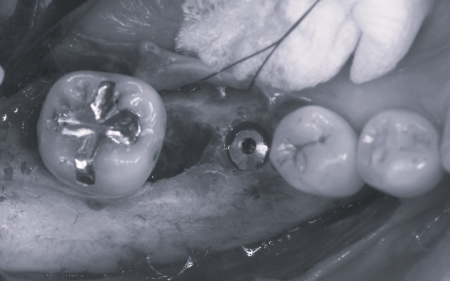

診断結果を踏まえ、まず下左右の第1大臼歯については抜歯したあとにインプラントで補う方法を提案しました。

さらに虫歯が再発していた左上奥歯については、虫歯をしっかりと取り除いたうえで被せ物による修復治療を提案しました。 それぞれのメリット・デメリットを丁寧に説明したところ、治療計画に同意いただきました。 まず、歯周基本治療から開始しました。 下左右の第1大臼歯を抜歯し、その部位にインプラントを埋め込む手術を行いました。同時に、インプラントの隣にある下の第2大臼歯に対して歯周組織再生療法を施しています。 また、左上の奥歯は虫歯を取り除いたあと、歯の形を整えて型取りを行い、最終的にジルコニアクラウンを装着しています。 段階的に治療を進め、すべての治療を終了しました。 |